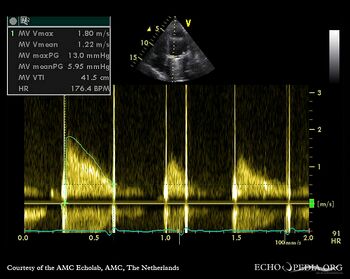

Case 108